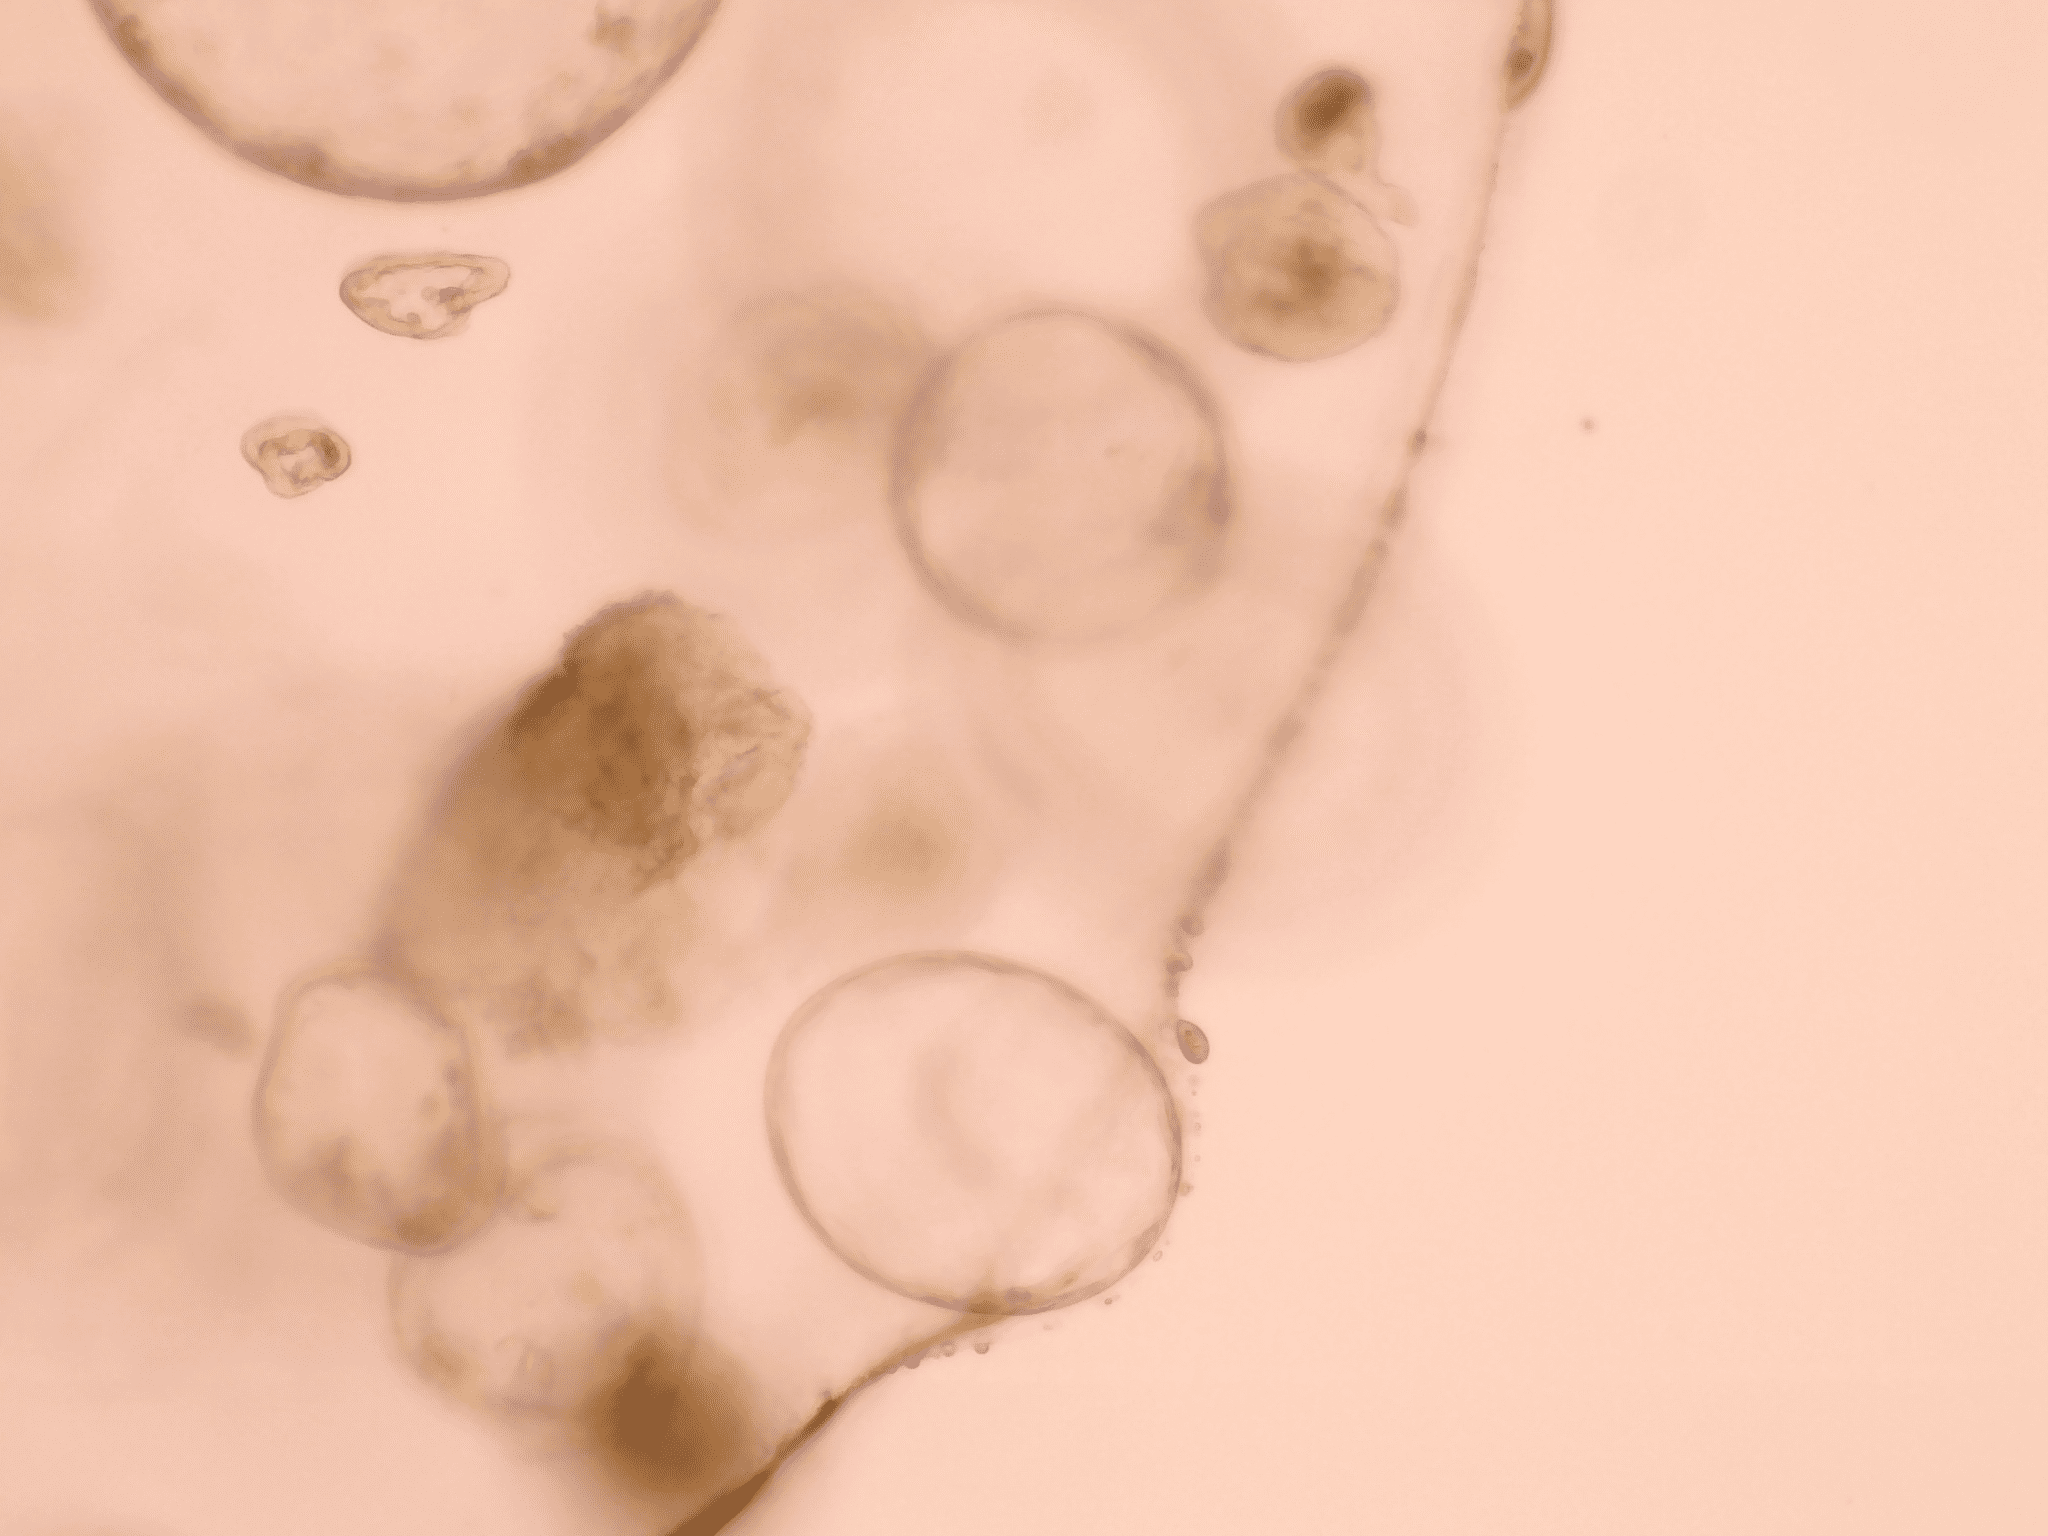

Reducing the stiffness of the PDAC organoid environment results in cells creating ductal-like structures as they develop from original more firm area into the softer area.